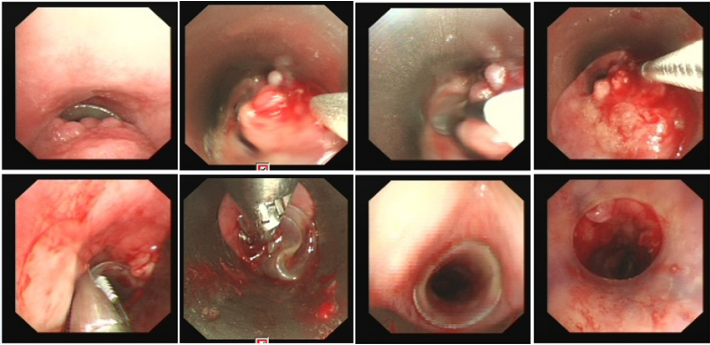

良性中心气道狭窄分为结构性和动力性(6种类型),结构性狭窄包括:管腔内生长(1型),外源性压迫(2型),瘢痕孪缩(3型),扭曲变形(4型);动力性狭窄包括:气道膜部向内膨出(5型),气道软化(6型)。对于动力性狭窄,应考虑用力呼气时的状态,通过操作者的判断,定出最合适、最接近的狭窄程度。治疗方法的制定不仅与气道狭窄程度和长度有关,还与是否存在狭窄过渡段有关。狭窄长度的计算应包括过渡区域。良性气道狭窄形态学分类的诊断方法应通过支气管镜所见及放射学检查来确定。每一个狭窄都可以用4个数字来表示,分别代表部位、类型、狭窄程度、狭窄长度。如:1344代表声门下瘢痕性挛缩性狭窄、狭窄程度>75%、狭窄长度>5 cm,这是一种非常难以处理的良性气道狭窄;2311代表气管瘢痕性蹼状网眼狭窄、狭窄程度<25%、狭窄长度<1 cm,这是一种比较容易处理的良性气道狭窄。热消融技术(APC、电凝、激光)是治疗增生性气道腔内病变(如良性肿瘤和单纯肉芽)的简单、快速的方法。但在治疗瘢痕狭窄病变时,其本身可对气道造成更重、更大范围的损伤,引起更为严重的肉芽组织增生和瘢痕形成,从而导致复发率高,且治疗次数的增加可导致狭窄病变范围增大并最终破坏软骨,导致气道塌陷,使患者彻底失去治愈的机会。电凝和APC仅适合管腔内生长的1型良性中心气道狭窄,并不适合其他类型良性中心气道狭窄的治疗。即便如此,基底部的处理也应避免使用此类治疗方法。针形电刀与气道黏膜接触面极小,不会造成损伤面扩大,瘢痕性气道狭窄的治疗宜选用针形电刀进行切割、松解。因激光也有切割的作用,因此也可选用激光治疗,钬激光、铥激光控制烧灼深度最浅可达0.4 mm,因此更适合良性瘢痕增生性气道狭窄的治疗。冷冻治疗分为冷冻切除(简称冻切,cryoextraction)及冷冻消融(简称冻融,cryoablation)。对于腔内生长的病变可采用冻切治疗,由于容易出血,其安全性不如热消融技术。对于瘢痕病变,冻切技术无法实施,则采用冻融治疗,冻融治疗不促进肉芽组织增生。与热消融相比,冷冻不易导致软骨损伤。通常在热消融治疗接近气道壁时或球囊扩张后采用冻融治疗处理剩余病变,有利于减轻瘢痕再狭窄发生的速度与程度。严重气道狭窄在开通气道前不要使用冻融,因其可引起气道水肿,加重气道狭窄,从而导致窒息。因此,冻融治疗后肺部体征监测及气管镜复查十分重要。机械扩张技术包括球囊扩张和硬质支气管镜扩张,并发症有气道撕裂、再狭窄、出血。(1)球囊扩张:是治疗瘢痕性气道狭窄最主要的技术,其优势是患者治疗后无明显的狭窄段延长,狭窄复发时再狭窄的程度比热消融治疗后轻得多,有利于维持气道复张的疗效。对气管黏膜损伤小,可以在软镜下应用,但需要中断通气。对于挛缩、韧性较强的瘢痕,可先用针形电刀进行切割以松解瘢痕;避免直接暴力球囊扩张,导致气道膜部的撕裂伤。(2)硬质支气管镜扩张:其优势是扩张时不需要中断通气,安全性更好。针对瘢痕肉芽组织增生导致介入治疗后的气道再狭窄,可采用气道狭窄部位局部应用药物的方法抑制瘢痕肉芽组织增生。介入治疗后气道再狭窄可选择的治疗药物有:糖皮质激素、丝裂霉素C、曲尼斯特、紫杉醇等。通过直接植入放射性物质(最常用铱-192)或经过可弯曲支气管镜近距离照射气道瘢痕肉芽组织,促使成纤维细胞凋亡。气道支架置入首选硅酮支架,禁用金属裸支架。支架治疗应作为良性气道狭窄最后选择的治疗技术,启动气道支架治疗的指征:①应用前述各种治疗方法疗效不佳,不能维持气道通畅;②在确定外科手术前临时放置;③外压性气道狭窄;④气道软化、塌陷且无法或不准备行外科手术治疗。病例1:17岁,女性,骨折术后肺炎插管,拔管后(2月14日)气道明显狭窄(图3)。2月15日评估:HR 113次/min,R 24次/min,静息下SpO2 97%(FiO2 50%),咳嗽及说话后喘鸣,有阵发性血氧下降。会诊后拟行急诊介入治疗。2月15日无痛气管镜示:声门下腔黄色及乳白色膜状坏死物,气管上段大量黄色坏死物并管腔重度阻塞,仅见小孔,以冷冻法清除坏死物后管腔通畅(图4)。术后气促明显改善,无需吸氧。病例2:77岁,女性,呼吸困难2个月,加重3天,于2023年12月2日入院(2023年9月气管插管,插管后20余天后拔管)。入院当天查体:HR 125次/min,R 30次/min,静息下SpO2 96%(高流量FiO2 30%),PaCO2 56 mmHg。患者术前影像如图5所示。12月3日查体:HR 140次/min,R 35次/min,BP 190/90 mmHg,SpO2 68%~75%(FiO2 100%),躁动不安,急查血气分析:PaCO2 89 mmHg。紧急床旁无创通气支持下气管镜:气管上段狭窄80%以上,较多黄白黏稠分泌物在狭窄口随呼吸摆动,予抽吸后SpO2升至98%,见狭窄处直径约3 mm,外径5.2 mm,软镜无法进入,遂置入导丝,10#球囊扩张多次,狭窄部位增宽,外径4 mm气管镜引导6.0号气管导管经口插管成功(图6)。插管后患者HR 98次/min,复查血气分析示PaCO2 41 mmHg,氧合指数300 mmHg以上。12月4日气管镜示:右鼻旁路进镜,缓慢退气管导管至声门,距声门3 cm处狭窄,直径7 mm,予12#球囊扩张1 min,2次,未见出血,扩张后直径约12 mm,地塞米松局部保留,气管导管复位(图7)。12月5日拔除气管导管。12月6日气管镜示:气管上段瘢痕狭窄(管径10~12 mm),少许膜状坏死、未见肉芽,予以清除坏死物,7点、11点冻融,术毕注入地塞米松5 mg(图8)。12月13日气管镜示:气管上段瘢痕狭窄(管径12 mm左右),少许膜状坏死、未见肉芽,予以清除坏死物,7点、11点冻融,术毕注入地塞米松5 mg(图9)。

12月8日复查胸部CT,气管管径较前明显增宽(图10)。患者于12月14日出院,于当地定期复查。病例3:80岁,男性,发现颈部肿块5年,咳嗽气促1个月入院(2024年1月6日)。2019年1月14日曾于外院置入气管硅酮支架。术前(1月6日):HR 95次/min,R 22次/min,静息下SpO2 97%(FiO2 29%),活动后喘鸣。1月8日硬镜示:气管上段膜部肉芽样新生物致管腔混合性重度狭窄(外压为主),冷冻+直钳清除气管上段膜部新生物(质韧,活检困难),术后直钳上调硅酮支架至气管起始部,完全覆盖狭窄处(图11),术后气促明显改善。术后病理:鳞状上皮化生,伴轻度非典型增生。1月12日凌晨1:09突发气促加重,喘鸣明显,HR 140次/min,BP 200/102 mmHg,R 35次/min,SpO2 97%(FiO2 35%)。紧急联系介入和麻醉团队进行急诊介入治疗,无痛喉罩下正压通气,患者喘鸣消失。支气管镜示:声门下腔水肿,气管起始部见大块坏死物堵塞管腔,随呼吸呈活瓣样,管腔明显狭窄,予冷冻+钳夹清理,支架未移位(图12)。